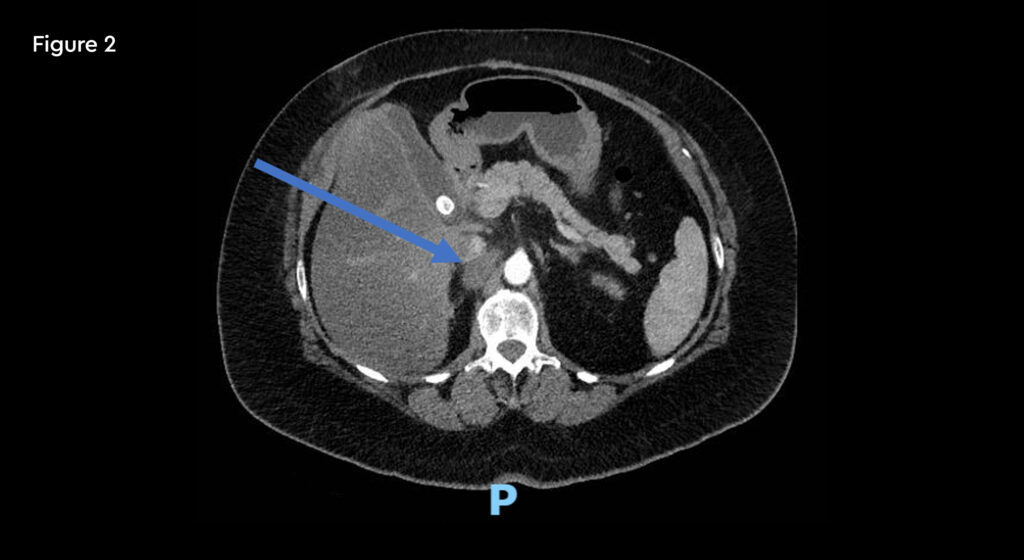

A 52-year-old female with metastatic renal carcinoma. At the time of referral for stereotactic ablative radiotherapy (SABR) she had oligoprogressive disease in a single lymph node beneath the right diaphragmatic crus (figure 1).

Fig 1: Pre-treatment CT scan showing right upper abdominal node measuring 25mm on 10th January 2020

Fig 2: Post-treatment CT scan (19mm) on 12th May 2020 10 weeks after completion of SABR

A follow-up CT scan at 10 weeks after SABR treatment showed a reduction in size of the node.